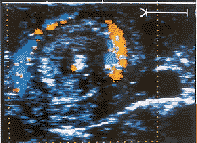

图1 肠旋转不良患儿的上腹横断面,示螺旋转包块

, http://www.100md.com

图2 同一断面的彩色多普勒图像(箭头示SMA)

肠扭转是肠旋转不良的常见合并症,其病理改变为肠管、肠系膜及SMV围绕SMA的顺时针旋转,以扭转360°最为多见,由于系膜血管的绞窄,造成肠管的缺血、坏死。二维超声可在肠系膜上血管的根部测及螺旋样包块,中央为SMA,周围是肠系膜及SMV形成的分层样结构[3,4],即“漩涡征”。彩色多普勒检查可见“漩涡征”中心为动脉样频谱,周围显示由内向外顺时针旋转的血流信号存在,周边可见多层旋转样血流信号,代表SMA、SMV的分支和属支随肠系膜而旋转,二维及彩色多普勒图像的结合构成了该病的独特超声征像。从技术上讲,超声诊断本病有一定难度,新生儿肠系膜血管很细,仅2~3 mm,“漩涡征”的直径也只有 15 mm左右,且前方通常有胃肠气体干扰。检查时应注意:①缓慢地逐步加压以获取清晰图像;②探头应自肠系膜上血管根部向下移动,直至SMA、SMV消失为止;③探头应放在上腹正中,自左或右方探测可造成人为血管位置及关系异常。